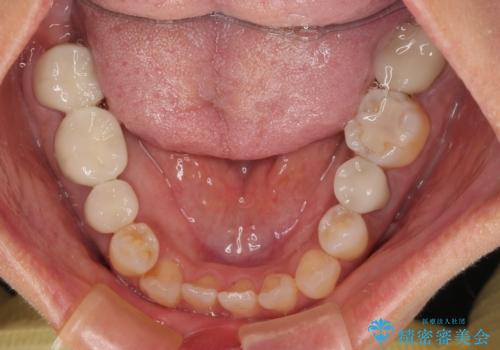

右下のむし歯が歯肉縁下に及んでおり、歯周外科処置(歯冠長延長術)を行った上で、根管治療を行い、状態を整えて補綴治療を行うこととしました。

新幹線で通院をされていたため、極力診療回数を減らして、一度にまとめて多くの処置を行うことで負担を軽減しました。